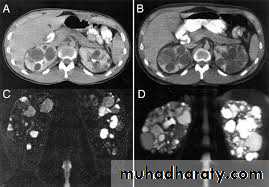

7.Renal agenesis8.Polycystic disease of the kidney infantile(AR) usually presented in the first few days of life with renal failure and enlarged kidneys . Adult(AD) presented in the third decade with loin pain, hematuria hypertension and renal failure , 25-50% have positive family history . It is most invariably bilateral , diagnosed by US or CT

• It represent 80-90% of all renal malignancy, peak age 55 year. It is bilateral in 2%. It metastasize to the lung, liver, bone(lytic expansile), regional LN, and adrenal glands• US: solitary mass bulging from the renal outline. It is usually iso- or hypoechoic compared to normal kidney. Most show some heterogeneity. It is of irregular outline. Necrosis will give areas of low echogenicity in the centre of large tumors.

• CT: spherical mass, often lobulated, usually isodense or hypodense compared to normal renal tissue, occasionally hyperdense. They enhance variably with intravenous contrast but almost always less than normal renal tissue. About 1/3 have calcifications.

• CT is the current method of choice for staging of RCC because:

• 1.it show the local direct spread

• 2.can demonstrate enlargement of drainage LN

• 3.show tumor growing along the renal vein into IVC.

• 4.diagnose liver, adrenal and pancreatic metastases